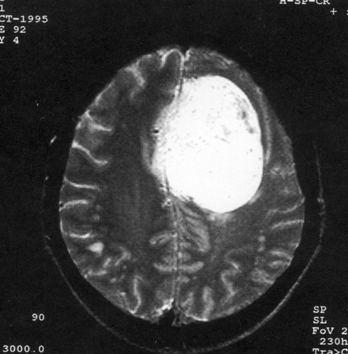

问题 病历摘要:??患者,男,40岁。发作性左下肢抽搐1年余,每次发作3~5分,每周发作1~2次。每次发作后感左下肢乏力,约半日后可自行恢复。既往身体健康。体检:神清,头顶部偏右有局限性骨性隆起(1.5×1.5cm),左鼻唇沟稍浅,伸舌居中。感觉、运动无明显异常。左浅反射减退,左下肢腱反射稍亢进,左Babinski征(-)。 下列关于脑膜瘤的叙述哪些是错误的?